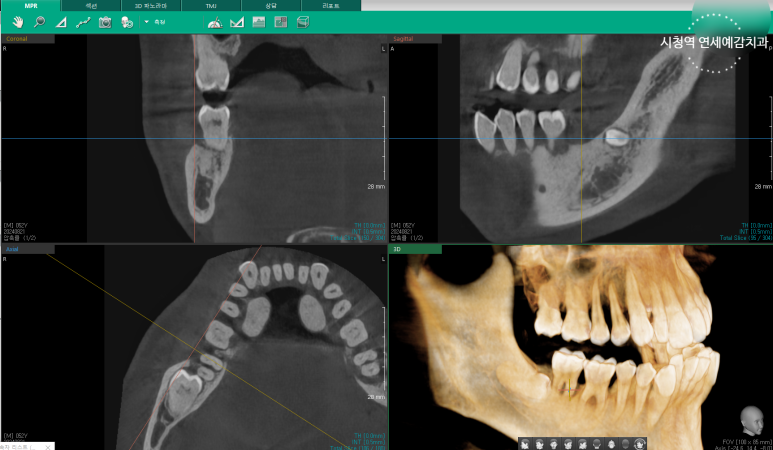

눈으로 체크 하고 엑스레이로 더블체크하며

크랙을 체크하는 기계,

더 필요한 부분은 3D CT도 촬영할 수 있게 필요한 장비들이 많이 구비되어 있습니다.

이렇게 최대한 기록을 많이 해놓아서

환자분들이 치아보험을 청구할 때 보험사와 분쟁이 생기지 않도록

최대한 대비합니다.